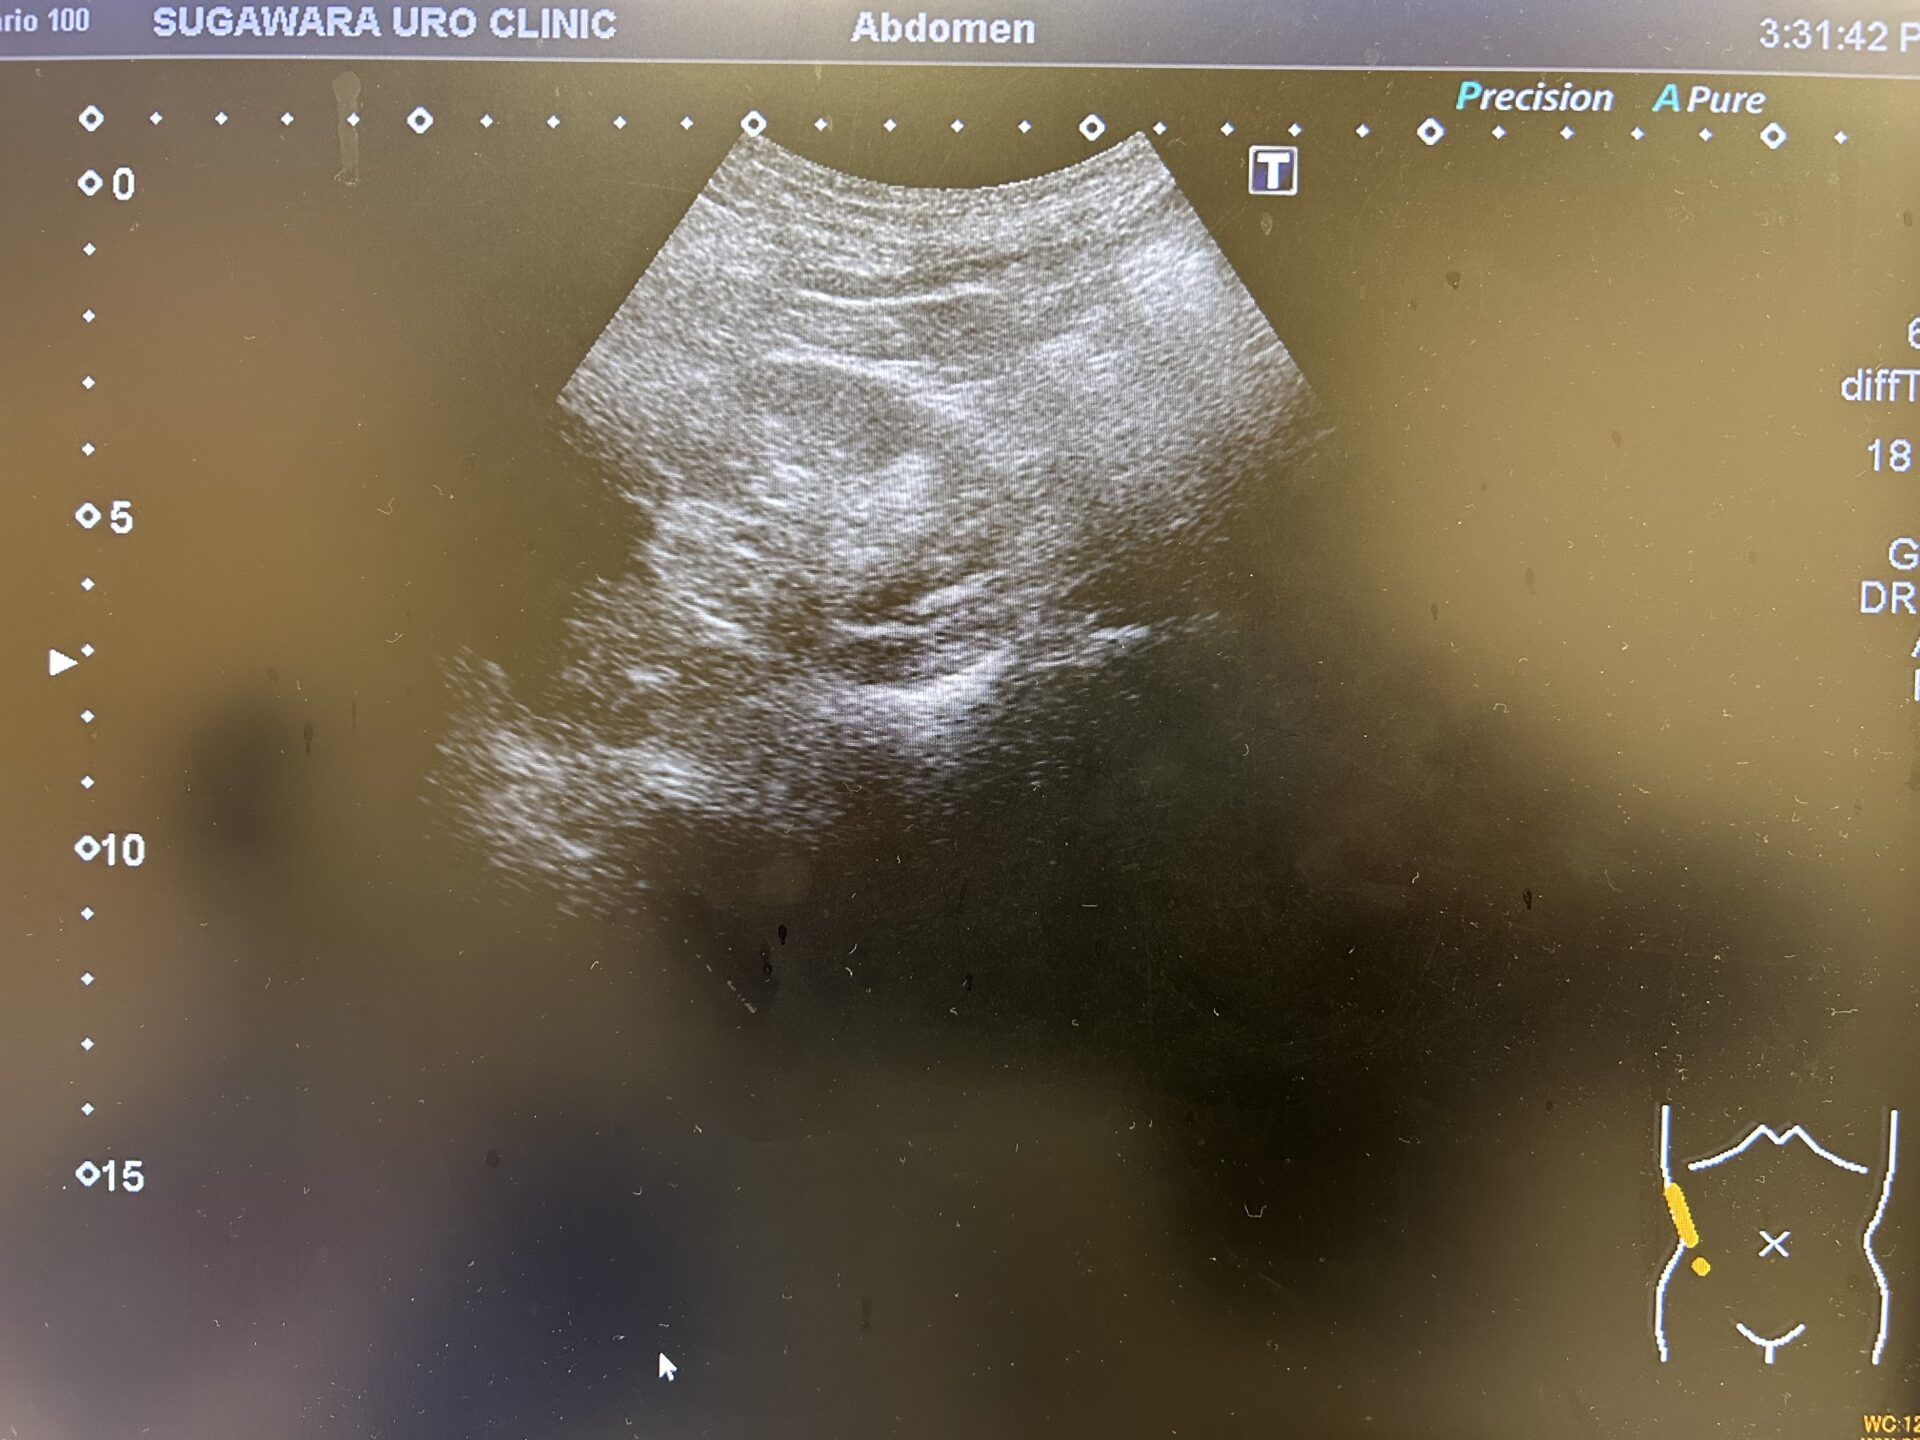

【今回の膀胱エコー:膀胱壁三角部右側に粘膜肥厚像を認めている】